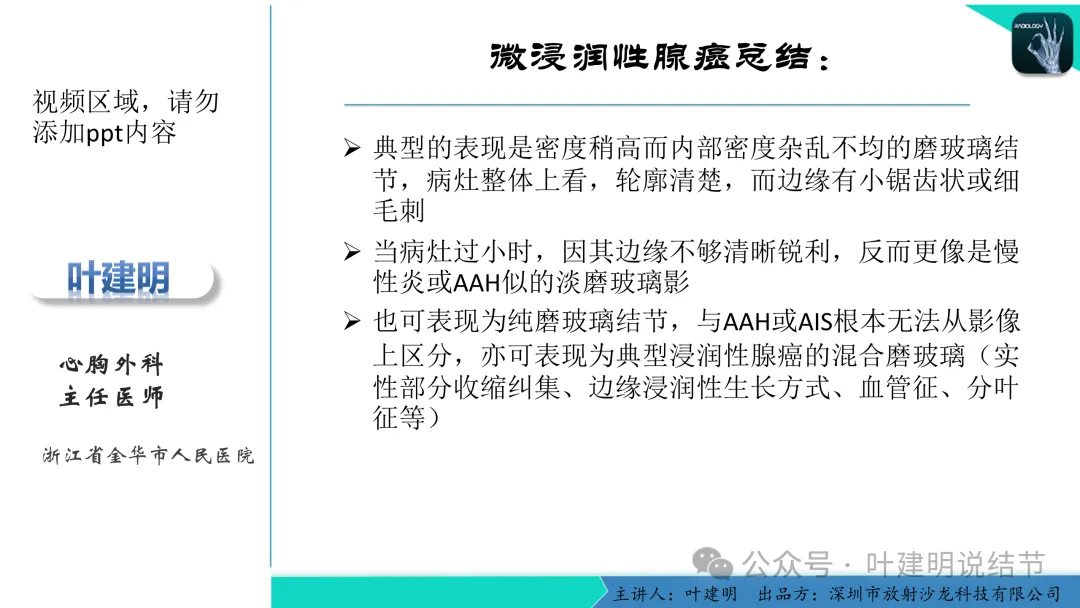

早在2020年时,我受邀在《放射沙龙》做过一个系列的精品课,当时专门总结分析过各类良恶性肺结节与肿块的影像特征,这是当时关于微浸润性腺癌影像特征的分析,今天看来仍基本不太需要改变,大家有兴趣的可以参考: